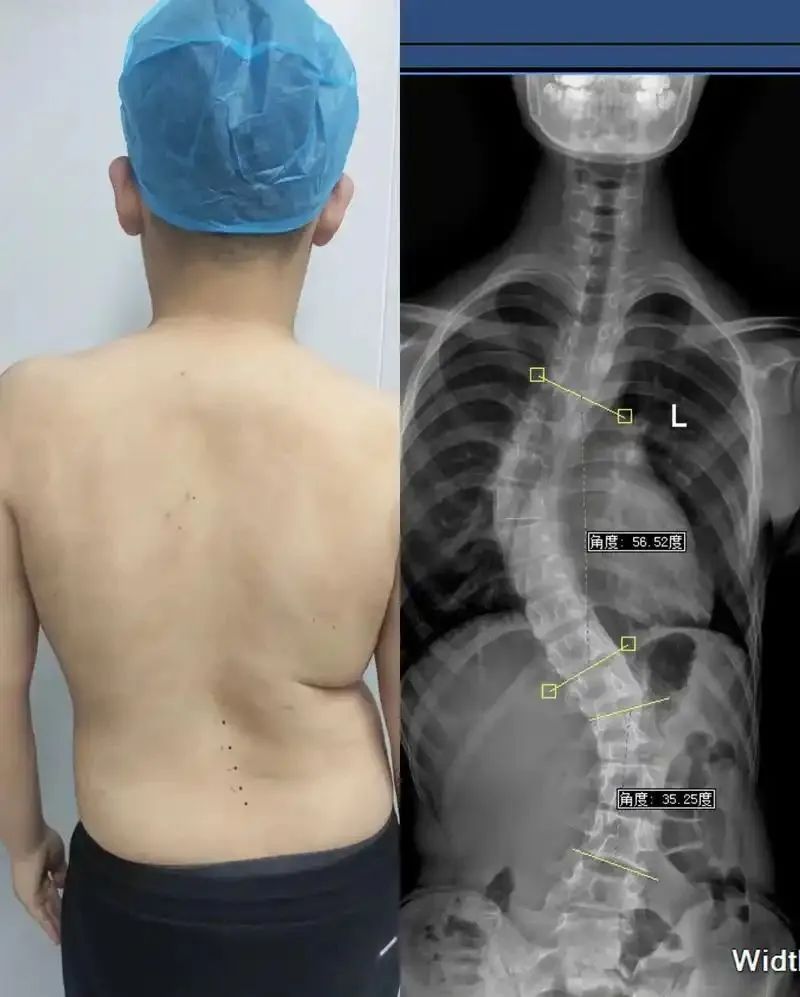

近些年,脊柱问题越来越严重,甚至越来越年轻化!

脊柱侧弯、脊柱炎、颈椎病、腰椎间盘突出...

从解剖学的角度来说,我们的脊柱上遍布神经,脊柱任何一节出了任何一点问题,都有可能影响到我们的视、听、平衡、肢体协调等。

本次石家庄线下课,就有好几位带着脊柱问题来到“长远脊柱”线下课现场的学员朋友。

现如今,有脊柱问题的人越来越多,脊柱病也越来越年轻化,而究其病因,很多都适合我们不良的生活习惯有关!